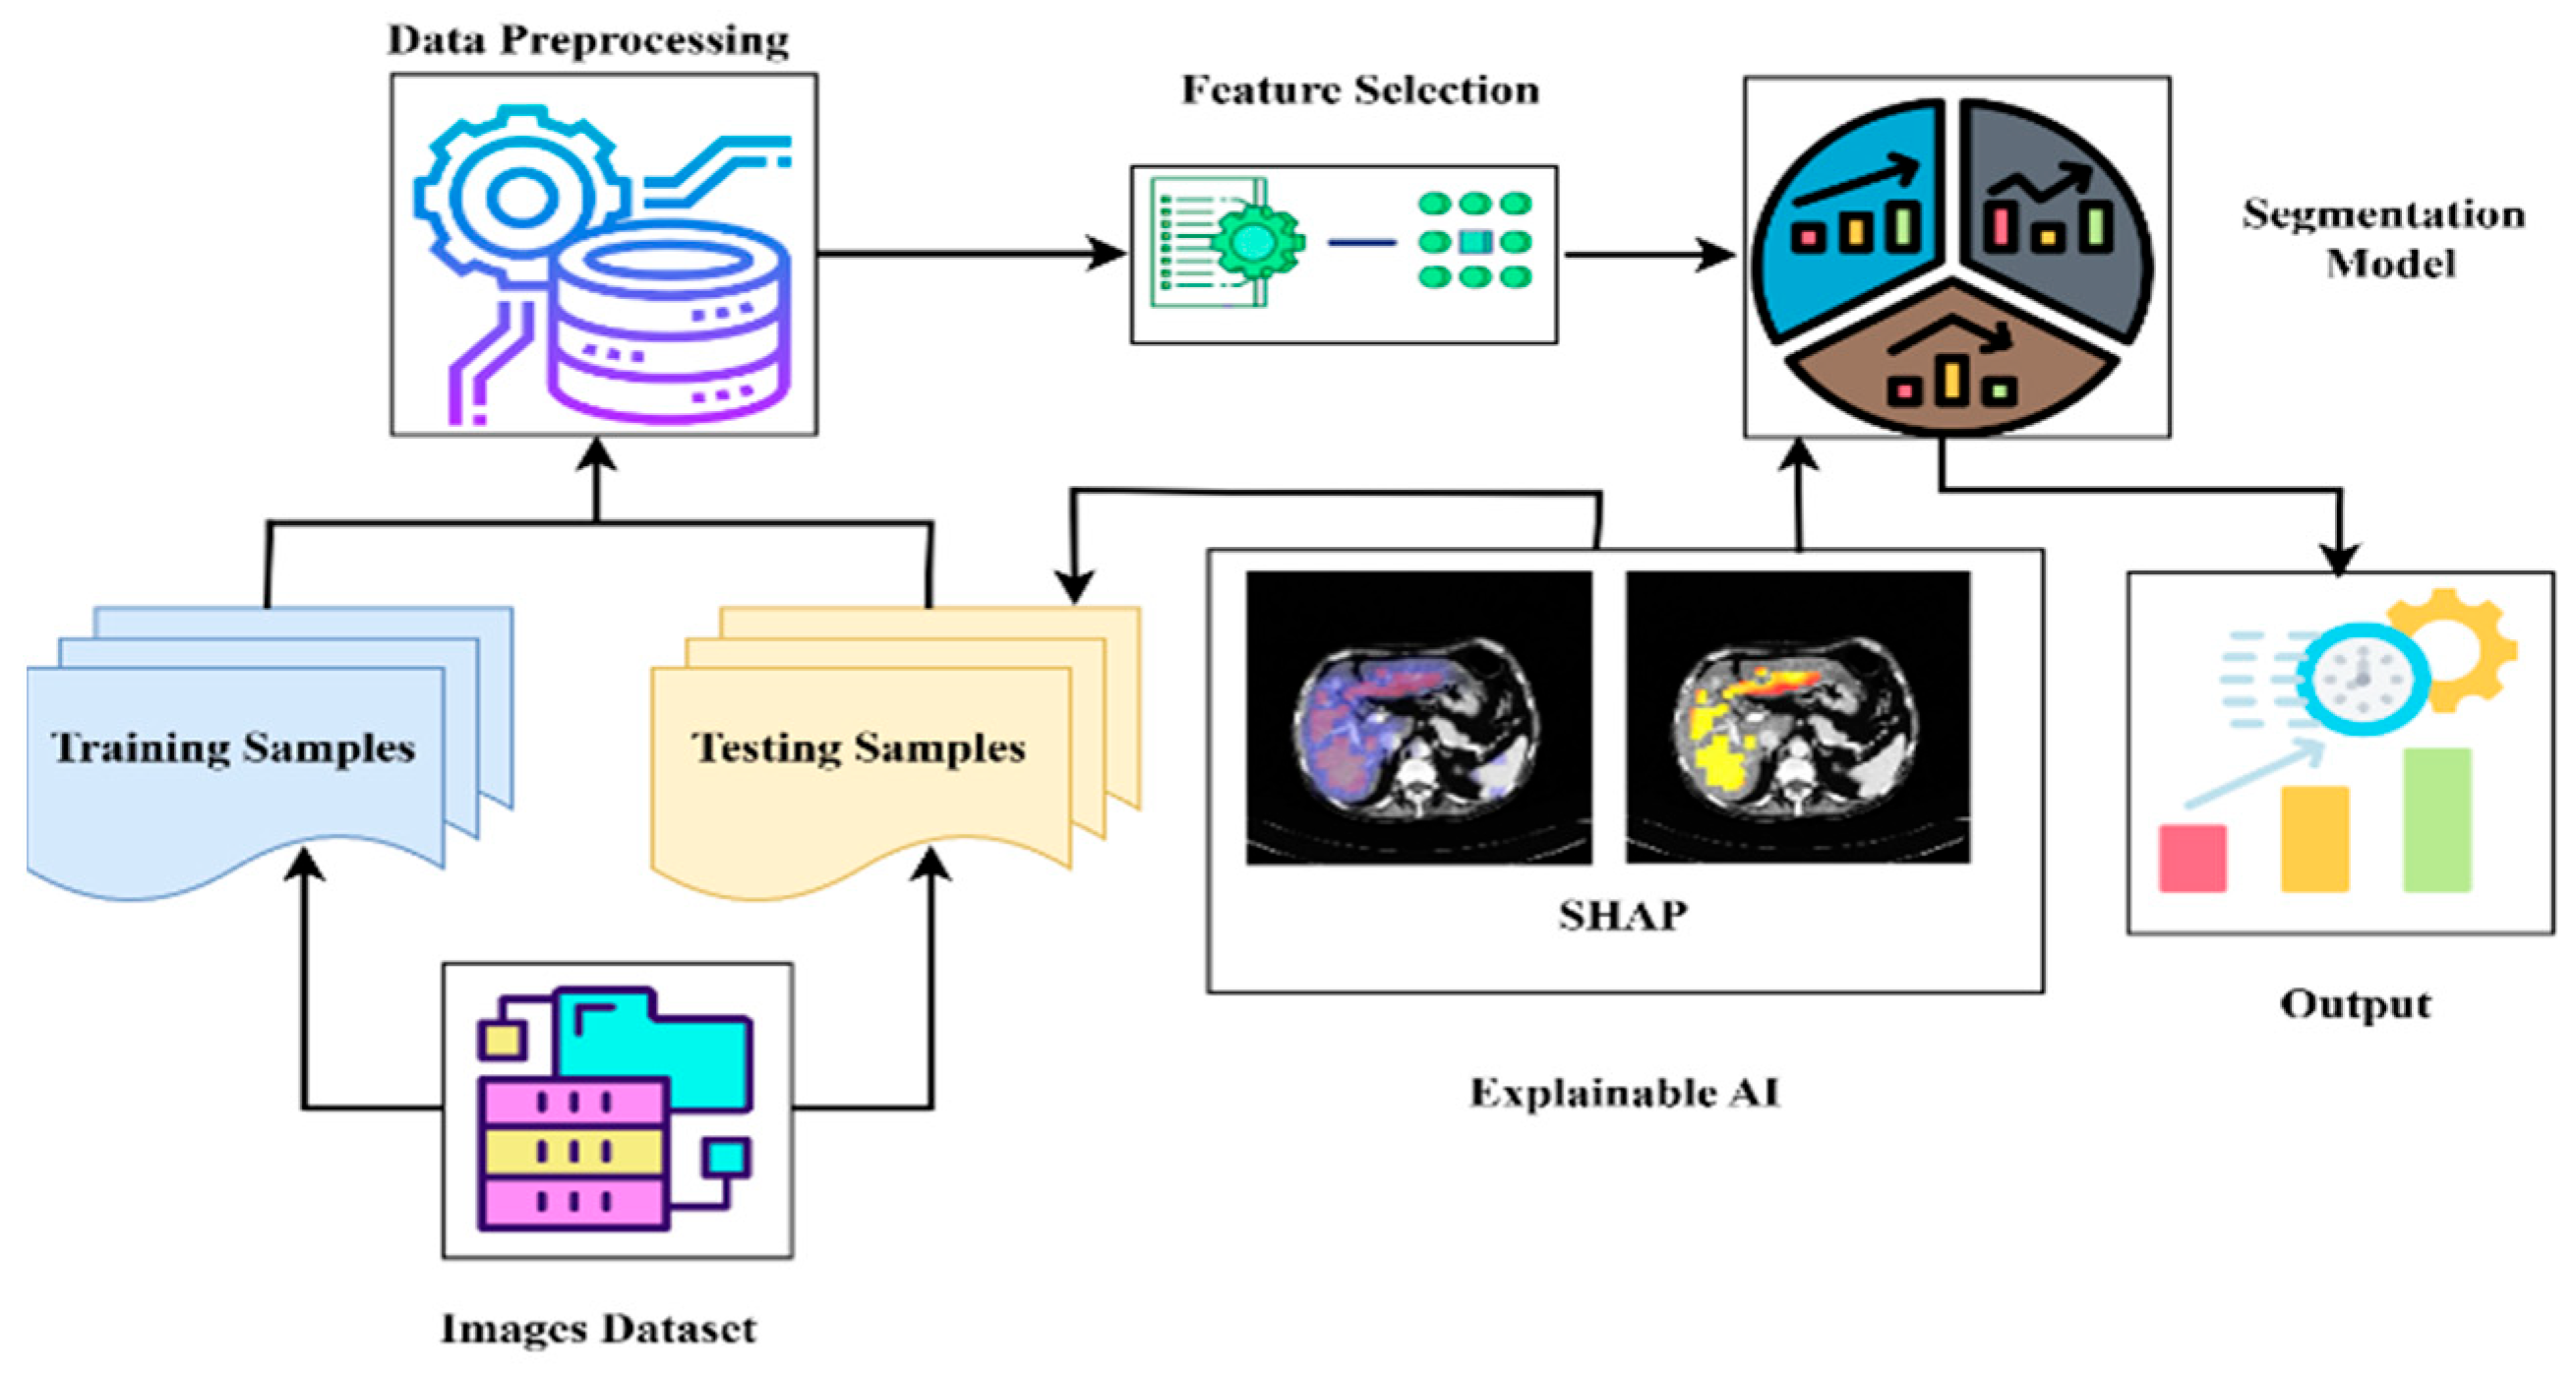

3.7. Explainable AI (XAI)

4.7. Explainable AI Analysis